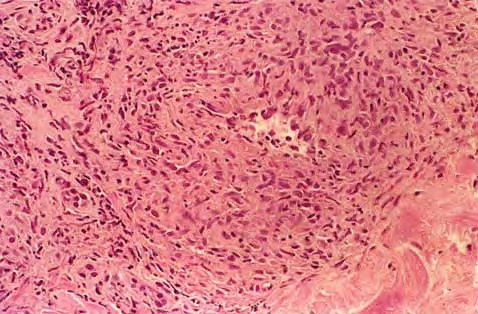

Graft versus Host Disease =داء رفض الطعم للمضيف Graft Versus Host Disease GVHD occurs in situations in which donor immunocompetent T cells transferred into allogenic hosts are incapable of rejecting them. The sources of the T cells include primarily peripheral blood stem cell and bone marrow transplants and, infrequently, unirradiated blood products , solid organ […]